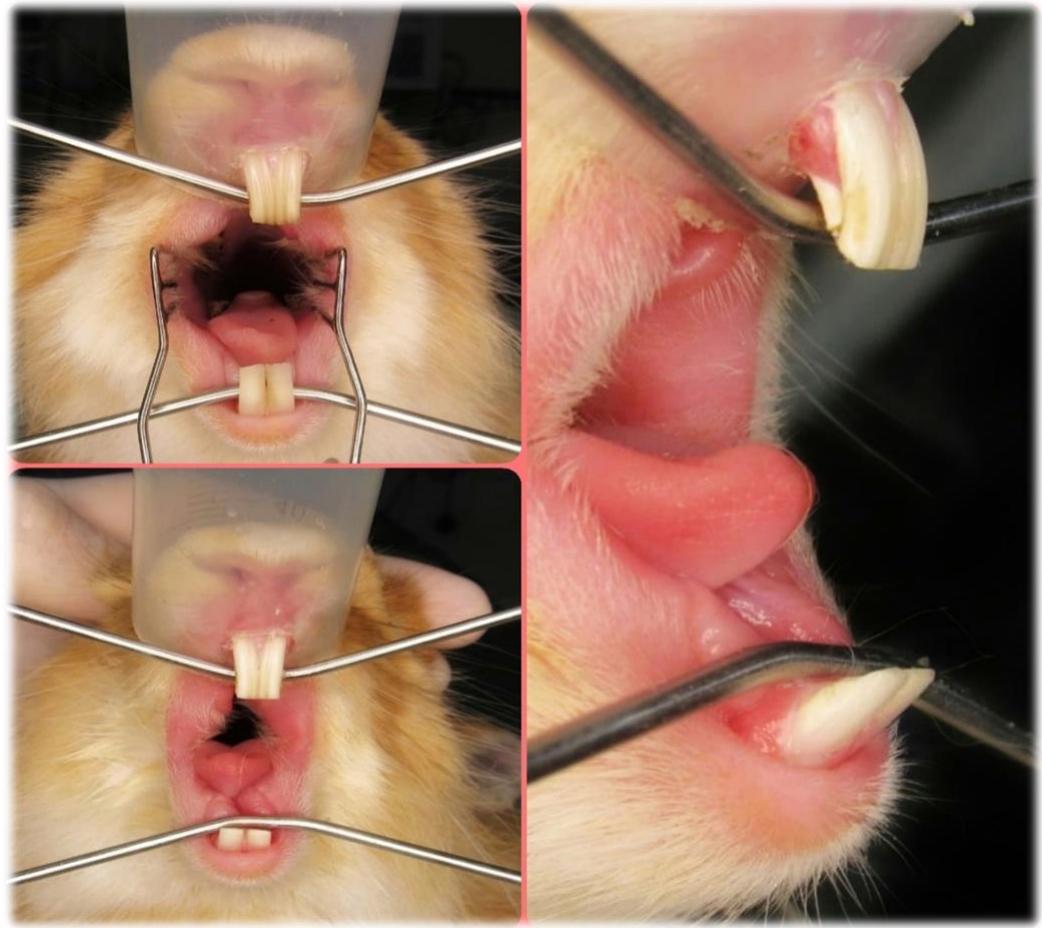

Paraiba uma coelha de aproximadamente 01 ano de idade, fêmea, inteira, pesando 1,9 kg, com histórico de ter sido perseguida no dia anterior por um cachorro no condomínio ondemora, e desde então ficou quieta e sem querer comer. O animal apresentava-se tranquilo ao exame físico, permitindo a manipulação, parâmetros fisiológicos sem alterações dignas de nota. Na avaliação clínica específica da cabeça constatou-se epífora no olho esquerdo, fato este que na anamnese a tutora relatou já estar presente antes da queixa principal ter ocorrido, a cavidade oral foi examinada com a visualização rostral do desalinhamento dos incisivos por meio do simples afastamento dos lábios (Fig. 4 e 5) e em seguida o animal foi deitado em decúbito dorsal no coloda tutora e utilizou-se um espéculo vaginal metálico (para a abertura das bochechas) e uma micro câmera (para registrar a imagem intra oral) (Fig. 6 e 7) onde visualizou-se a formação de pontas dentárias no sentido lingual dos pré molares mandibulares direito e esquerdo. Ao ser questionada sobre a dieta, a tutora relatou que era exclusivamente ração peletizada e frutas (banana, pera e eventualmente pepino e couve).

Fig. 4: Desalinhamento oclusal dos incisivos inferiores. Vista Rostral.

Fig. 6: Ponta dentária em pré molar inferior esquerdo (seta vermelha). Vista rostral intraoral.

Fig. 5: Desalinhamento oclusal dos incisivos inferiores. Vista Lateral.

No dia 13 de Setembro de 2021 no Hospital Veterinário Jefferson Ricardo, situado em João Pessoa, Paraíba, o paciente foi operado. O tratamento consistiu na redução da coroa clínicados incisivos por meio de odontosecção com disco de corte diamantado (Fig. 11 e 12) e dos pré molares e molares usando a peça reta com uma broca carbide esférica ${ \mathsf { n } } ^ { \circ } \ 8,$ buscando a oclusão correta dos incisivos, que acontece quando os incisivos inferiores se encontram entre os incisivos superiores anteriores e posteriores e uma angulação próxima dos $10 ^ { \circ }$ para os pré molares e molares, que é o preconizado na literatura VESTRAETE, Frank (2005). Essa verificação foi feitapor meio do registro fotográfico utilizando-se uma micro câmera anexada ao celular e também uma câmera digital (Fig. 13, 14 e 15 a,b,c).

Fig. 7: Pré molar inferior direito. Vista rostral intraoral.

Fonte: Arquivo pessoal do autor Fig. 15: a. Incisivos aspecto inicial; b. Incisivos aspecto final, vista rostral. c. Incisivos aspecto final vista lateral.